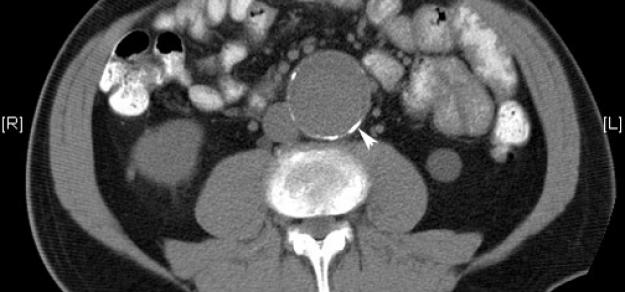

Prescripción de metformina y aneurisma aórtico

03 abril 2019

Heart, 1 de abril de 2019 la prescripción de metformina podría limitar la expansión de la AAA entre los pacientes con esta enfermedad, y podría estar involucrada con una menor incidencia de aneurisma aórtico y eventos de aneurisma aórtico